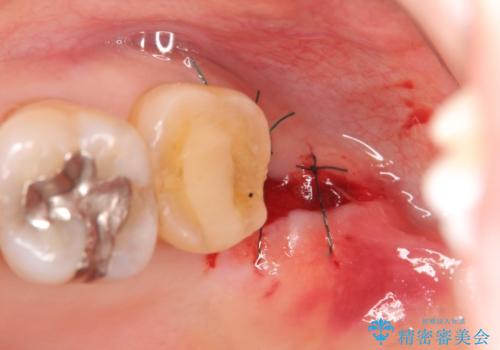

クラウンの将来的な虫歯の再発を防ぐために周囲の歯ぐきを切除することで歯の高さを出し安定した歯周環境にしたのち噛み心地の良いゴールドクラウンを製作します。

クラウンを装着した歯の虫歯の再発を防ぎ長い予後を期待するために削った箇所をしっかりとかぶせる適合の良さが必要はもちろんですが、セメントの漏洩を防ぐためにクラウンの十分な支台高径を歯周外科を行い獲得しました。